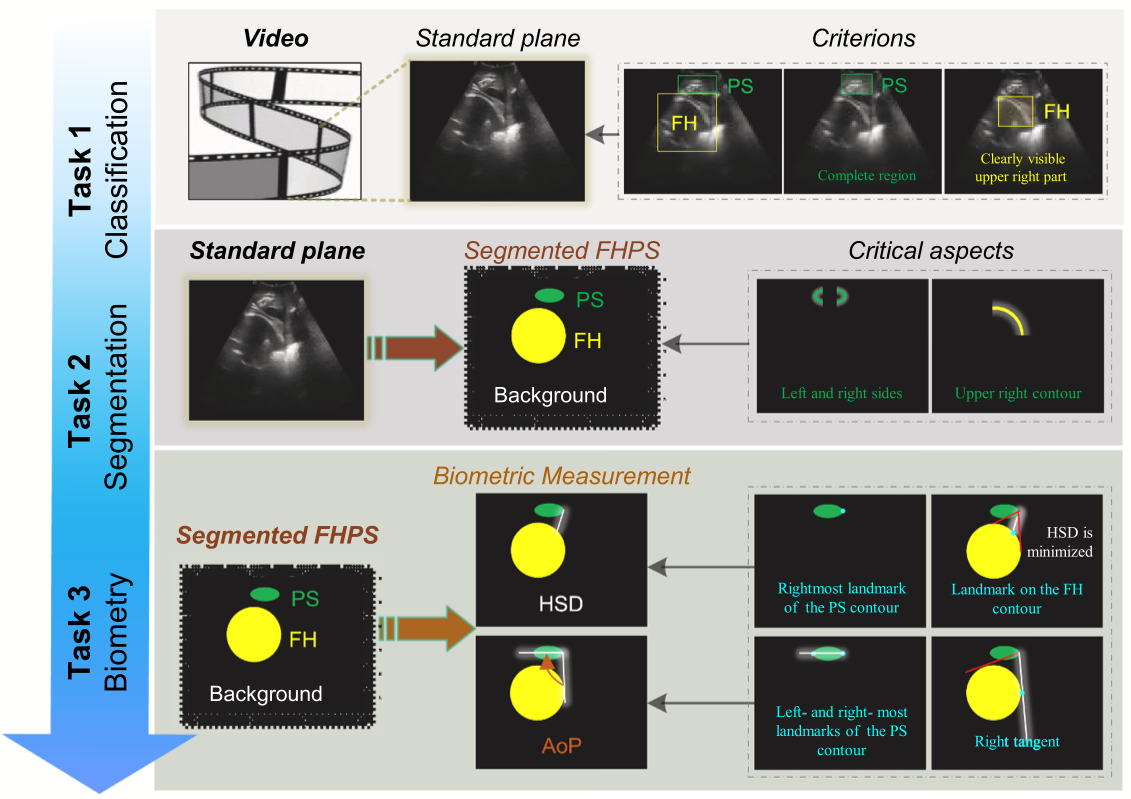

Beyond benchmarks of IUGC: Rethinking requirements of deep learning method for intrapartum ultrasound biometry from fetal ultrasound videos

Automated Fetal Biometry Assessment with Deep Ensembles using Sparse-Sampling of 2D Intrapartum Ultrasound Images